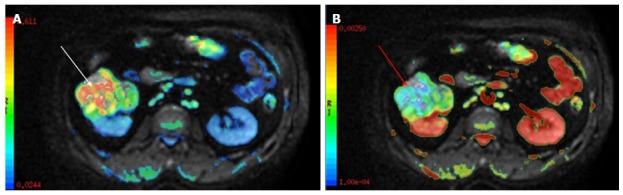

"Personalized oncology" is a multi-disciplinary science, which requires inputs from various streams for optimal patient management. Humongous progress in the treatment modalities available and the increasing need to provide functional information in addition to the morphological data; has led to leaping progress in the field of imaging. Magnetic resonance imaging has undergone tremendous progress with various newer MR techniques providing vital functional information and is becoming the cornerstone of "radiomics/radiogenomics". Diffusion-weighted imaging is one such technique which capitalizes on the tendency of water protons to diffuse randomly in a given system. This technique has revolutionized oncological imaging, by giving vital qualitative and quantitative information regarding tumor biology which helps in detection, characterization and post treatment surveillance of the lesions and challenging the notion that "one size fits all". It has been applied at various sites with different clinical experience. We hereby present a brief review of this novel functional imaging tool, with its application in "personalized oncology".

“个性化肿瘤学”是一门多学科科学,为实现最佳的患者管理,需要各个领域的投入。现有治疗方式取得了巨大进展,除形态学数据外,提供功能信息的需求也日益增加,这推动了成像领域的飞跃发展。磁共振成像随着各种更新的磁共振技术取得了巨大进步,这些技术提供了至关重要的功能信息,并正成为“放射组学/放射基因组学”的基石。扩散加权成像就是这样一种技术,它利用了水质子在给定系统中随机扩散的趋势。这项技术通过提供有关肿瘤生物学的重要定性和定量信息,彻底改变了肿瘤成像,有助于病变的检测、特征描述和治疗后监测,挑战了“一刀切”的观念。它已在不同部位应用,并积累了不同的临床经验。在此,我们简要综述这一新型功能成像工具及其在“个性化肿瘤学”中的应用。